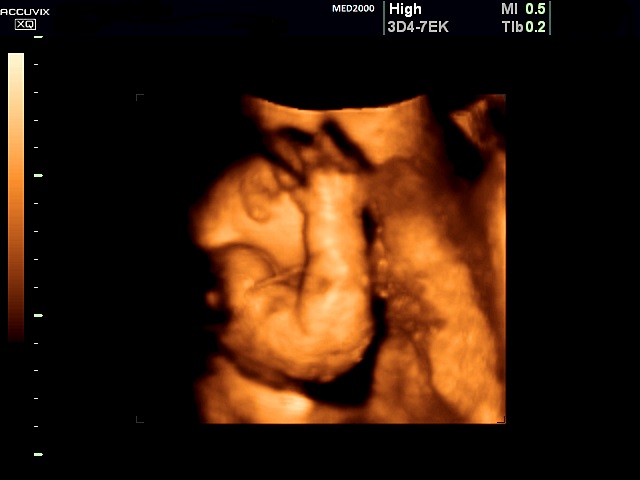

E' caratterizzata da un accorciamento prevalente del femore (rizomelia), anche se sono interessate tutte le ossa lunghe (micromelia) e le ossa delle mani e dei piedi (brachidattilia); la testa è grossa (macrocefalia/macrocrania) con bozze frontali prominenti e ponte nasale depresso. La diagnosi ecografica precoce non è possibile. Spesso infatti l'acondroplasia può essere sospettata o confermata solo in fase avanzata di gravidanza in quanto la micromelia si manifesta tardivamente con un accrescimento delle ossa lunghe inferiore al 5° percentile evidente solo nel III trimestre. La diagnosi può essere facilitata in caso di storia familiare positiva per tale patologia. Alcuni studi hanno riportato l'associazione con la NT aumentata.

1. micromelia: è il segno più evidente, con gli arti inferiori al 5°percentile dopo la 20a-22a settimana; vi è anche brevità rizomelica che interessa principalmente i femori.

2.    femore corto con coscia che presenta un aumentato spessore del sottocute.